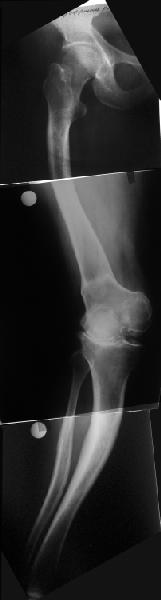

Обратилась дама 57 лет с намерением протезировать коленный сустав. Имется грубая осевая деформация (см. рентгенограммы). Встает вопрос насчет улучшения оси конечности. Даже с мобилизацией на пртяжении при таком вальгусе малоберцовому нерву может не поздоровиться. Уважаемые коллеги, как лучше провести коррекцию? Какой сегмент, на каком уровне, на какую величину? Что бы Вы исправили до протезирования, что можно оставить и сделать вместе с замещением сустава?

На бедре дистальный отдел в сгибательной установке после, видимо, когда-то сделанной корригирующей остеотомии. Не надо ли на том же уровне все-таки "разогнуть" бедро до протезирования? Сам протез, наверно, можно поставить в большем или меньшем "сгибании", но весь дистальный эпиметафиз бедра и все нижележащее оказывается кзади от механической оси бедра. Насколько это допустимо, не ведет ли к расшатыванию протеза? Или можно как-то рассчитать такой наклон протеза, что он компенсирует это смещение?

Это один из самых сложных вариантов для эндопротезирования, т.к. мы имеем деформацию бедренной кости в трех проекция, думаю, что есть и

ротационная деформация, плюс к этому - деформация голени. Однозначно в таких случаях, в отличии от возможностей при эндопротезировании ТБС необходимо выполнить корригирующие остетомии на двух уровнях. Что касается сгибательно установки мыщелков бедра - думаю, что это не является проблемой, особенно если на операции будет испрользован заднестабилизированный протез. Относительно вальгуса - все не так однозначно - возможно, что деформация слегка преувеличена за счет проекционной установки из-за ротационной деформации. Поэтому планирование операции необходимо будет делать только после коррекции деформации.